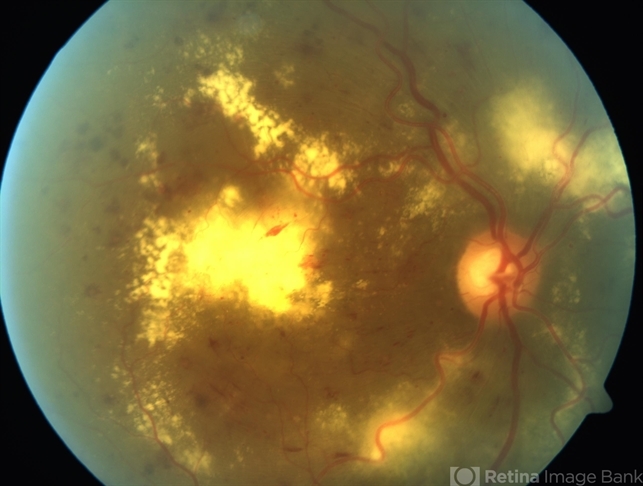

- clinically significant macular edema (CSME)

- 65-year-old type 1 diabetic female found to have macular edema.